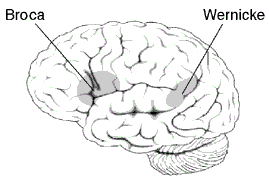

Localizationist approaches aim to classify the aphasias according to their major presenting characteristics and the regions of the brain that most probably gave rise to them.[30][31] Inspired by the early work of nineteenth century neurologists Paul Broca and Carl Wernicke, these approaches identify two major subtypes of aphasia and several more minor subtypes:

- Expressive aphasia (also known as "motor aphasia" or "Broca's aphasia"), which is characterized by halted, fragmented, effortful speech, but relatively well-preserved comprehension. Damage is typically in the anterior portion of the left hemisphere,[32] most notably Broca's area. Individuals with Broca's aphasia often have right-sided weakness or paralysis of the arm and leg, because the left frontal lobe is also important for body movement, particularly on the right side.

- Receptive aphasia (also known as "sensory aphasia" or "Wernicke's aphasia"), which is characterized by fluent speech, but marked difficulties understanding words and sentences. Although fluent, the speech may lack in key substantive words (nouns, verbs, adjectives), and may contain incorrect words or even nonsense words. This subtype has been associated with damage to the posterior left temporal cortex, most notably Wernicke's area. These individuals usually have no body weakness, because their brain injury is not near the parts of the brain that control movement.

- Conduction aphasia, where speech remains fluent, and comprehension is preserved, but the person may have disproportionate difficulty where repeating words or sentences. Damage typically involves the arcuate fasciculus and the left parietal region.[32]